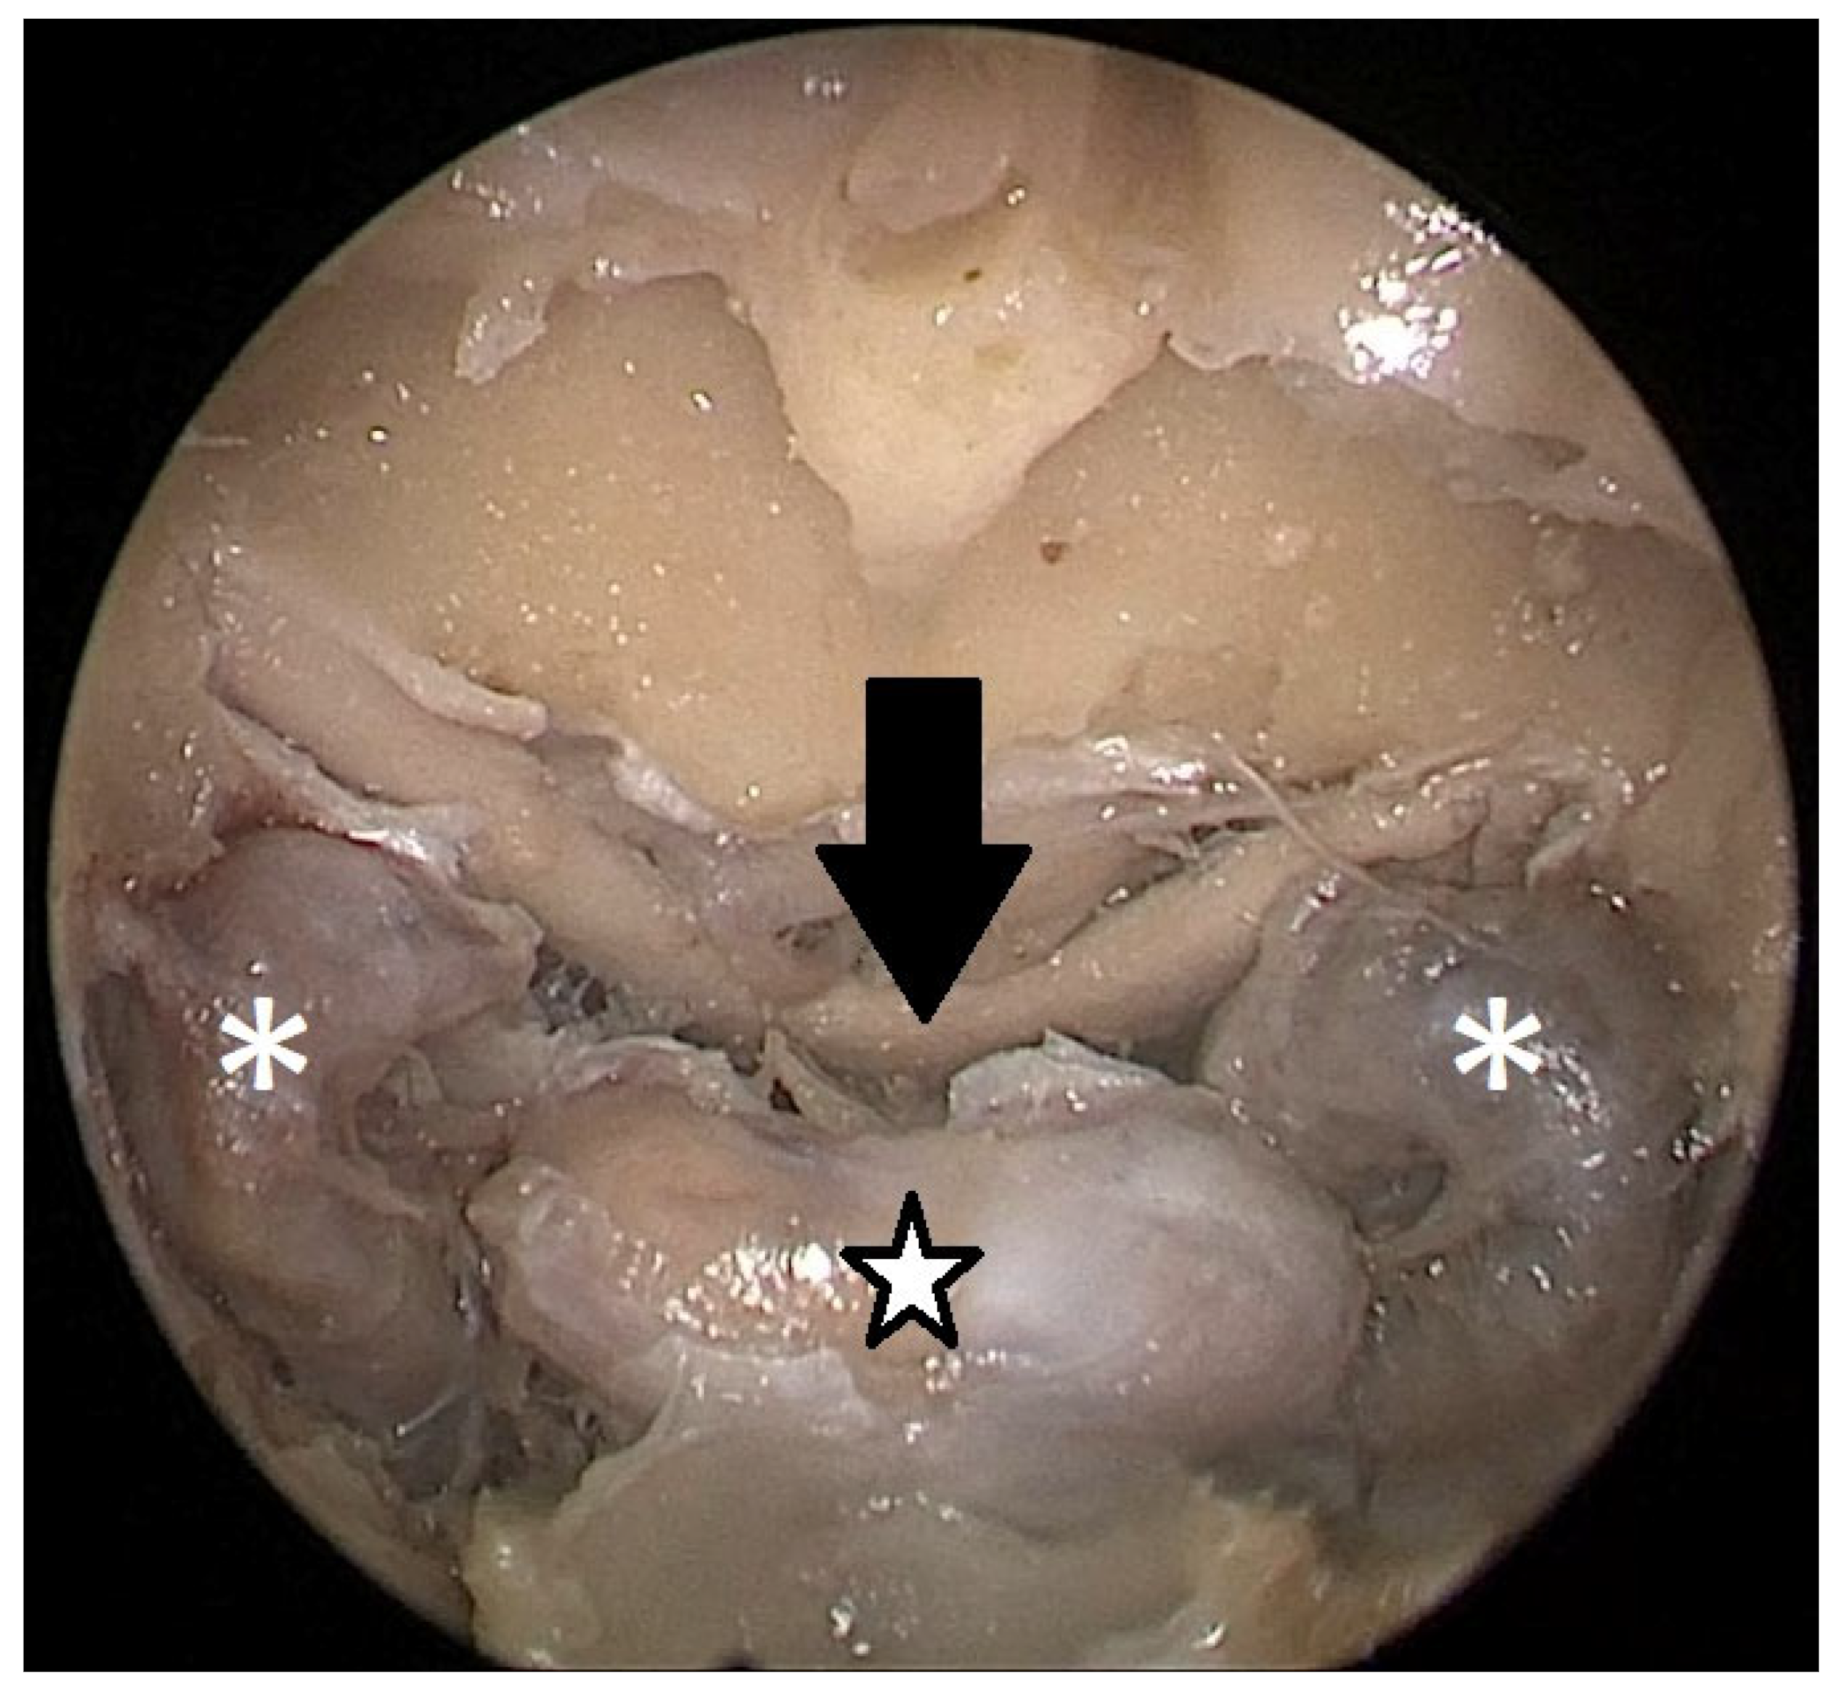

Cadaver pituitary surgery: On each of the two cadaveric heads, we used the paraseptal binostril approach for the sphenoid sinus. A 30° Storz endoscope (Karl-Storz, Austria, Vienna) was used. The head was mounted in a Mayfield cranial stabilization device. The surgery started with a lateralization of the inferior and medial turbinates. The anterior sphenoid wall and ostium to sphenoid sinus were identified. Using the straight suction with a marked scale, 1 cm and 2 cm distances from the anterior sphenoid wall were measured and marked with a scalpel on the posterior part of the septum. Using a scalpel, Kerrison punch, and backbiter punch, a posterior septal resection 1 cm from the anterior wall of the sphenoid was performed. We continued with the wide opening of the sphenoid cavity and resection of the intersphenoidal septum and the full exposure of the posterior wall, both ICAs, and optocarotic recesses (OCR). The posterior wall of the sphenoid sinus and dura were resected to better identify anatomic landmarks, with both ICAs, pituitary gland, chiasma, and optic nerves visible at the end of a resection (Figure 4). The straight suction was inserted into the sphenoid sinus so that the instrument’s tip was in the most lateral position in the sphenoid sinus without infracturing the rest of the nasal septum. A picture was taken in this position to evaluate the most lateral part of the sphenoid sinus that could be reached with a straight instrument with a 1 cm septal resection without infracturing the nasal septum (Figure 5). Enlargement of the septal resection to 2 cm from the anterior sphenoid wall was performed with a backbiter punch and scalpel. The straight suction was inserted into the sphenoid sinus so that the instrument’s tip was in the most lateral position in the sphenoid sinus without infracturing the rest of the nasal septum. A picture was taken in this position to evaluate the most lateral part of the sphenoid sinus that could be reached with a straight instrument, with a 2 cm septal resection, without infracturing the nasal septum (Figure 6).

According to the CT scan measurement on the cadaveric heads, a 1 cm resection of the posterior part of the nasal septum was enough to reach the medial edge of the ICA with a straight instrument, while a 2 cm resection was enough to reach the lateral edge of the ICA. Transnasal endoscopic surgery of the cadaveric heads proved the CT scan findings to be true. A 1 cm resection of the posterior part of the nasal septum was enough for the surgeon to reach the medial side of the ICA without infracturing the nasal septum with the straight instrument. A 2 cm resection was enough for the surgeon to reach the lateral edge of the ICA without infracturing the nasal septum. An approach with a 1 cm resection is sufficient for safe tumor extraction in non-extended cases. The same results were observed in both cadaveric heads. Subjective evaluation of the maneuverability and overview of the operated area was better with a 2 cm resection.

Each head was operated on twice. First, a binostril approach and a 1 cm posterior septal resection were performed. This allowed us, in both cadavers, to comfortably reach the medial part of the carotids bilaterally with straight suction. This resection size would be sufficient for a safe tumor extraction in non-extended tumors. Then, a 2 cm extension of the septal resection was performed. A more extensive resection allowed us to reach the lateral margin of the ICA bilaterally. It also gave us better maneuverability and an overview of the operated area.

Figure 5. Opened sphenoidal sinus, endoscopic view, straight suction (black asterisk) reaching the medial border of ICA (white asterisk) with a 1 cm septal resection.